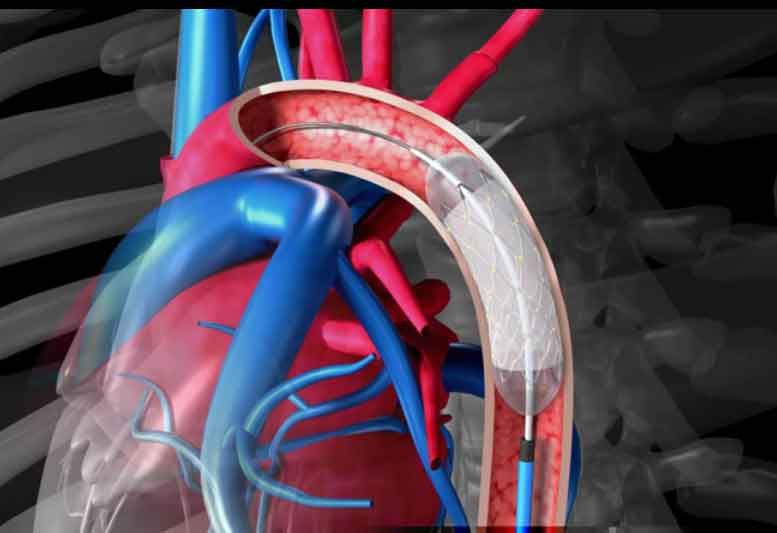

Utilizando un tubo largo y delgado denominado “catéter” que lleva un pequeño globo en la punta, se logra mediante el hinchado del mismo dilatar la arteria comprimiendo la placa contra la pared arterial

La realización del procedimiento y su resultado final se visualiza mediante la inyección repetida de contraste en las arterias coronarias o Coronariografía.

El procedimiento consiste en introducir un alambre delgado (catéter guía), en una arteria de la pierna, arteria femoral o del brazo generalmente la arteria radial, dirigiéndolo a la zona del estrechamiento (estenosis) arterial coronaria.

El catéter globo pasa a través del catéter guía, situándose y dilatándose en el lugar de la obstrucción Después del tratamiento se retiran ambos catéteres y se efectúa una compresión prolongada sobre la ingle, para evitar un hematoma en la arteria femoral

Actualmente la angioplastia con balón se complementa siempre con la colocación de un estent.

El estent es una malla metálica de forma tubular que se implanta en la zona de la arteria obstruida. El estent montado sobre un catéter que tiene un globo en la punta, se introduce en la arteria y se coloca en el lugar del estrechamiento arterial, al inflarse el globo el estent queda libre y abierto. A continuación se retira el globo desinflado dejando el estent en su lugar. La incidencia de reestenosis con éste procedimiento es de un 10%.